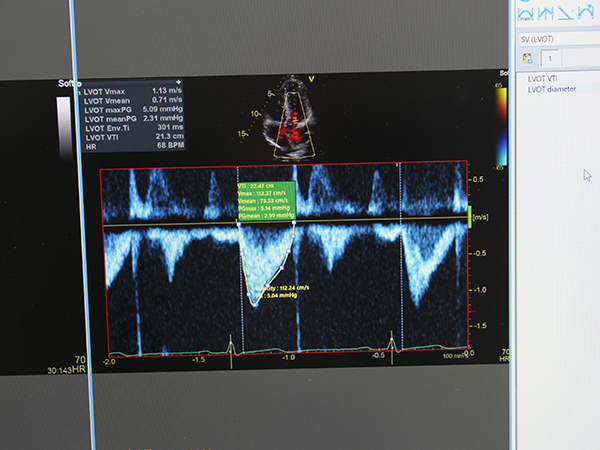

オリジナルDICOM画像の高速配信など,使いやすさを重視して開発が行われているGOODNET 7。今回のITEMでは,DICOMビューワのGoodView,WebソリューションGOODNETWebに今後追加する予定での新機能,エコー計測を紹介した。非侵襲的な検査のニーズが高まるとともに,構造的心疾患(structural heart disease:SHD)のインターベンションの適応が拡大している。こうした状況の中で心臓超音波検査に求められる役割は重要性を増しており,医師や臨床検査技師,診療放射線技師は検査だけでなく,その後の解析処理を行う機会も増えている。間もなく実装されるエコー計測は,GOODNET 7のサーバにある2D,ドプラ,Mモードなど超音波画像を用いて,GoodViewやGOODNETWebが利用できる電子カルテ端末から,EDV,ESV,SV,VTIといったデータを,簡単なマウス操作で自動計測できる。この機能は,複数の端末から解析処理を行いたいというユーザーからの要望に応える形で開発された。なお,GOODNET 7では,他社製の解析アプリケーション搭載システムとの連携にも対応している。心臓超音波検査向けのシステムとしては,TomTec Imaging Systems社製「TomTec-Arena」と組み合わせて使用できる。このため,簡易的な解析はGoodViewやGOODNETWebで行い,より高度な解析にはTomTec-Arenaで処理するといった,目的に応じた使い分けが可能となる。

「GoodView」や「GOODNETWeb」に追加される“エコー計測”機能

“エコー計測”はVTIなどを自動で計測